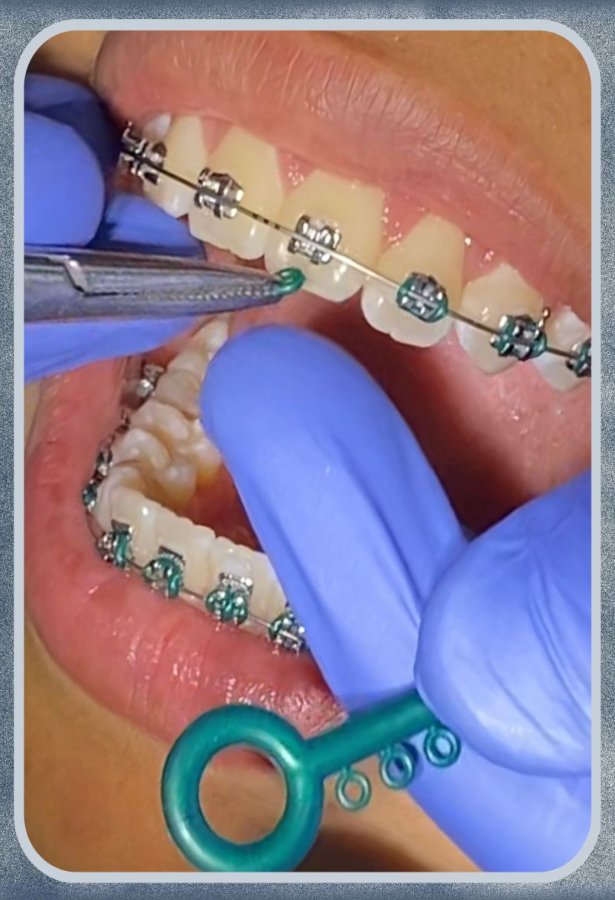

La ortodoncia es la especialidad odontológica que integra las necesidades funcionales de la oclusión con la estética dental y facial incluyendo balance y armonía facial.